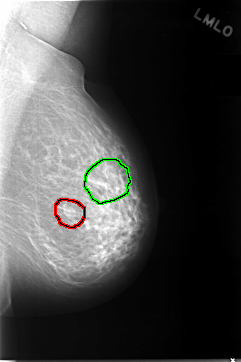

FILE: C_0038_1.LEFT_CC.OVERLAY

TOTAL_ABNORMALITIES 2

ABNORMALITY 1

LESION_TYPE MASS SHAPE OVAL MARGINS ILL_DEFINED

ASSESSMENT 4

SUBTLETY 3

PATHOLOGY BENIGN

TOTAL_OUTLINES 1

BOUNDARY

ABNORMALITY 2

LESION_TYPE CALCIFICATION TYPE FINE_LINEAR_BRANCHING DISTRIBUTION CLUSTERED

ASSESSMENT 5

SUBTLETY 4

PATHOLOGY MALIGNANT